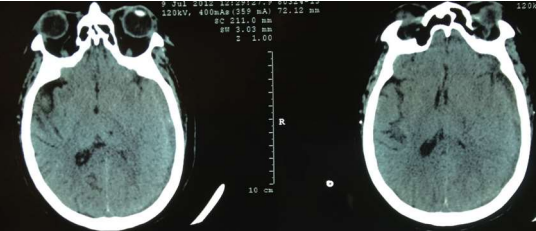

Fig 1,2,3,4,5,6,7,8,9,10,11,12,13,14,15

Thirty eight out of Eighty-two patients were treated conservatively and were studied (25 men; 13 females, mean age, 64.8 years). The average thickness of the hematoma was 18 mm, the mean midline shift was 4.7 mm, and the average attenuation value of bleed on computed tomography scan was 33.5. Thirty-eight were treated successfully with steroid treatment, whereas 44 patients required surgery. The female gender, less midline shift, less density (Hounsfield units) was noted to be associated with successful medical treatment. We propose a grading based on the total score given to the midline shift and density.

Figure 1

Figure 2

Figure 3

Figure 4

Figure 5

Figure 6

Figure 7

Figure 8

Figure 9

Figure 10

Figure 11

Figure 12

Figure 13

Figure 14

Figure 15